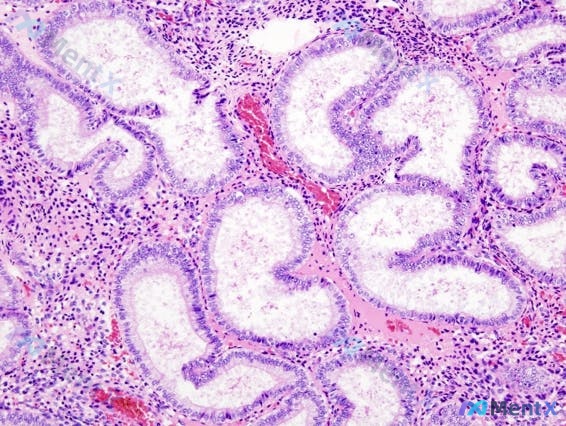

最近看到一个很有意思的病例,影像和病理初看有点「矛盾」,整理了一下分析思路和大家分享。 病例基本信息 39岁女性,因「症状性子宫肌瘤」拟行全子宫切除术,术前进行内膜评估。 关键检查结果 1. 经阴道超声(子宫矢状面) - 子宫肌层回声尚均匀,未见明显局灶性低回声/高回声团块 - 内膜重点异常: -...